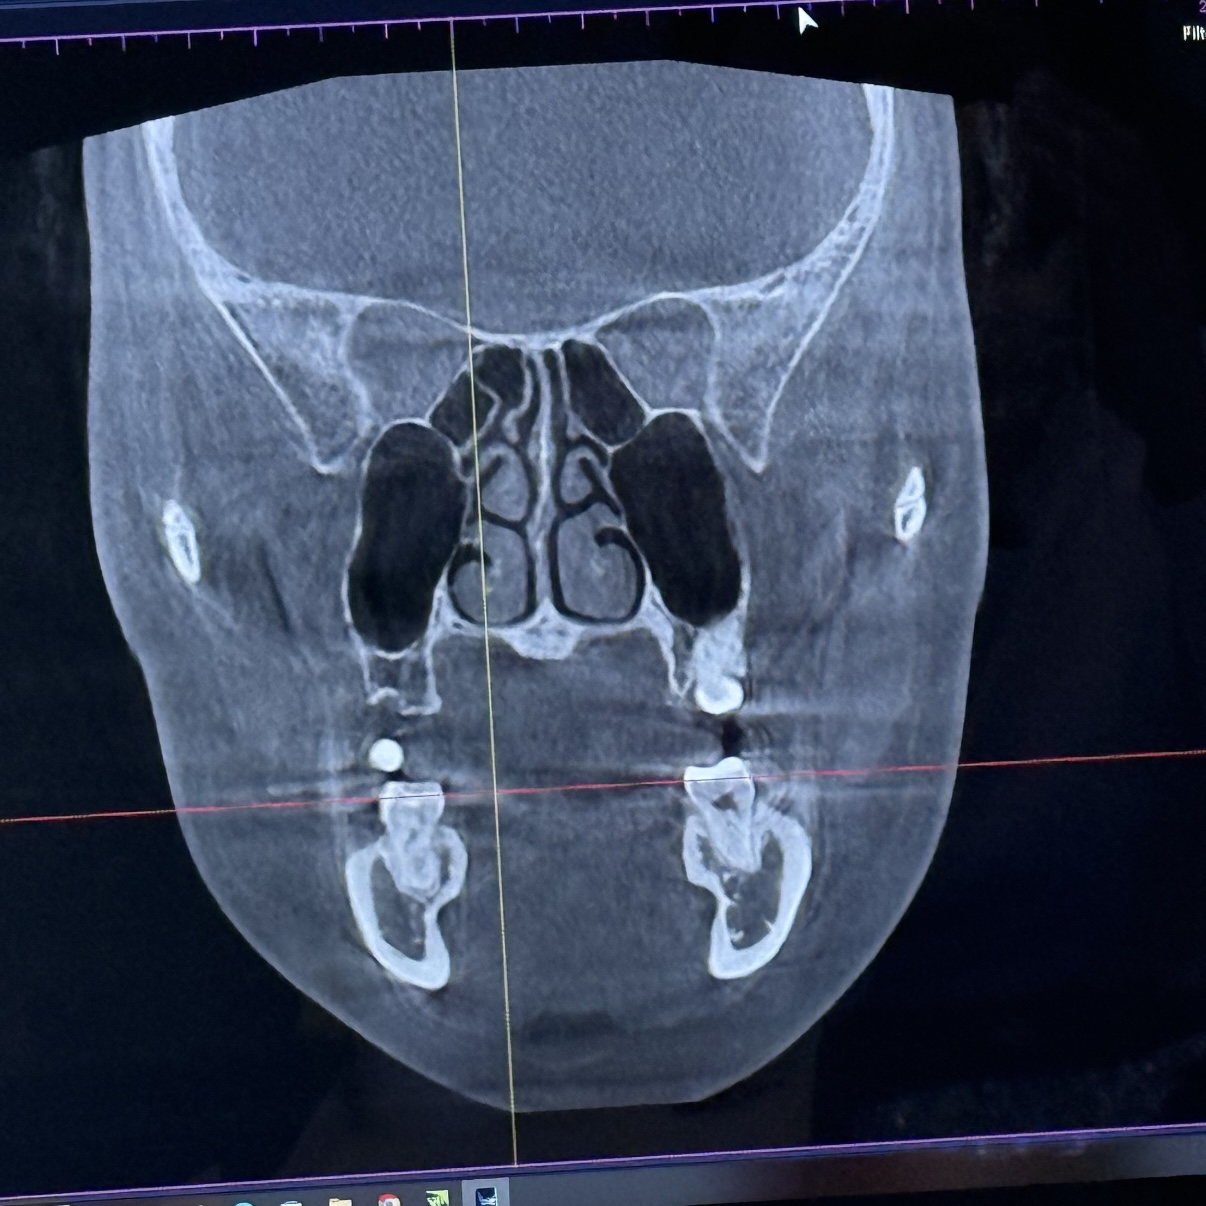

이정도면 얼지흡 하는게 나을까?

얼지흡 병원마다 말이 달라서 ㅠㅠㅠ

키빼몸 110인데 마른비반이라 체지방 30이야.. 얼굴형은 죽어도 안 빠져 ㅜ 넘 스트레스야